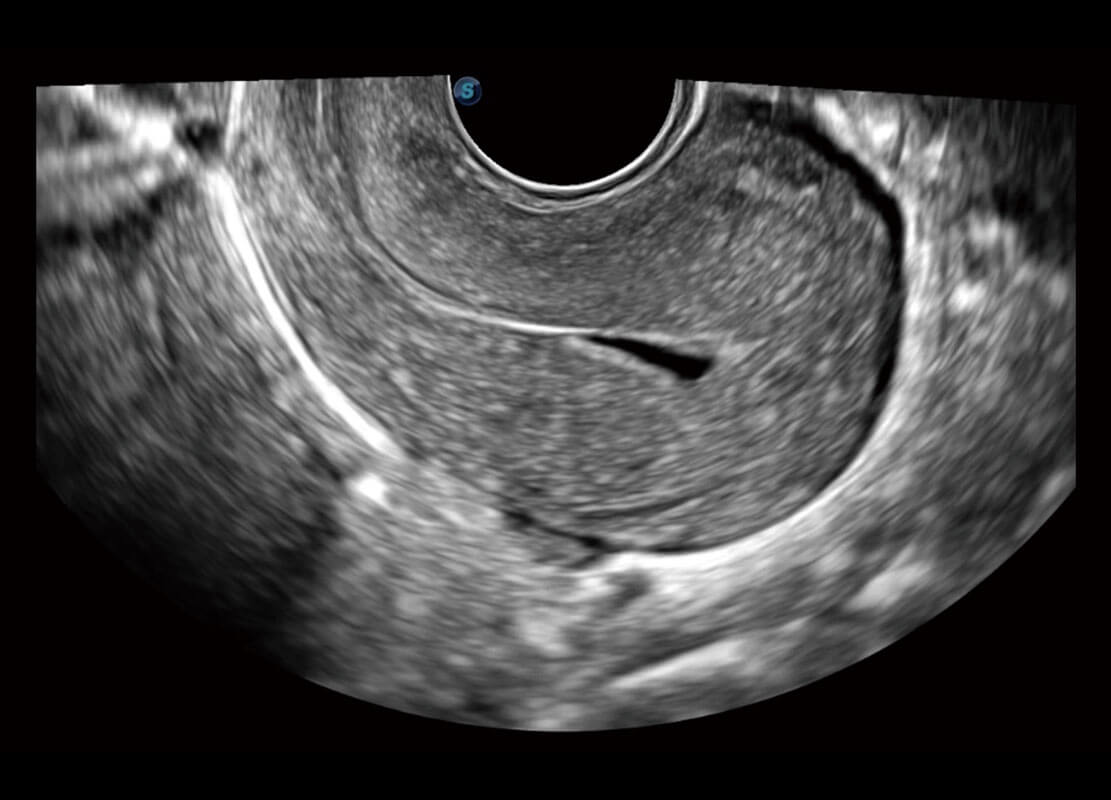

P60優(yōu)異的圖像質(zhì)量搭載??铺筋^,在婦科基礎(chǔ)疾病的診斷、卵泡生長的監(jiān)測、輸卵管通暢情況的判別等方面為您提供生殖應(yīng)用方案。

腔內(nèi)婦科-宮腔分離

腔內(nèi)婦科-卵巢